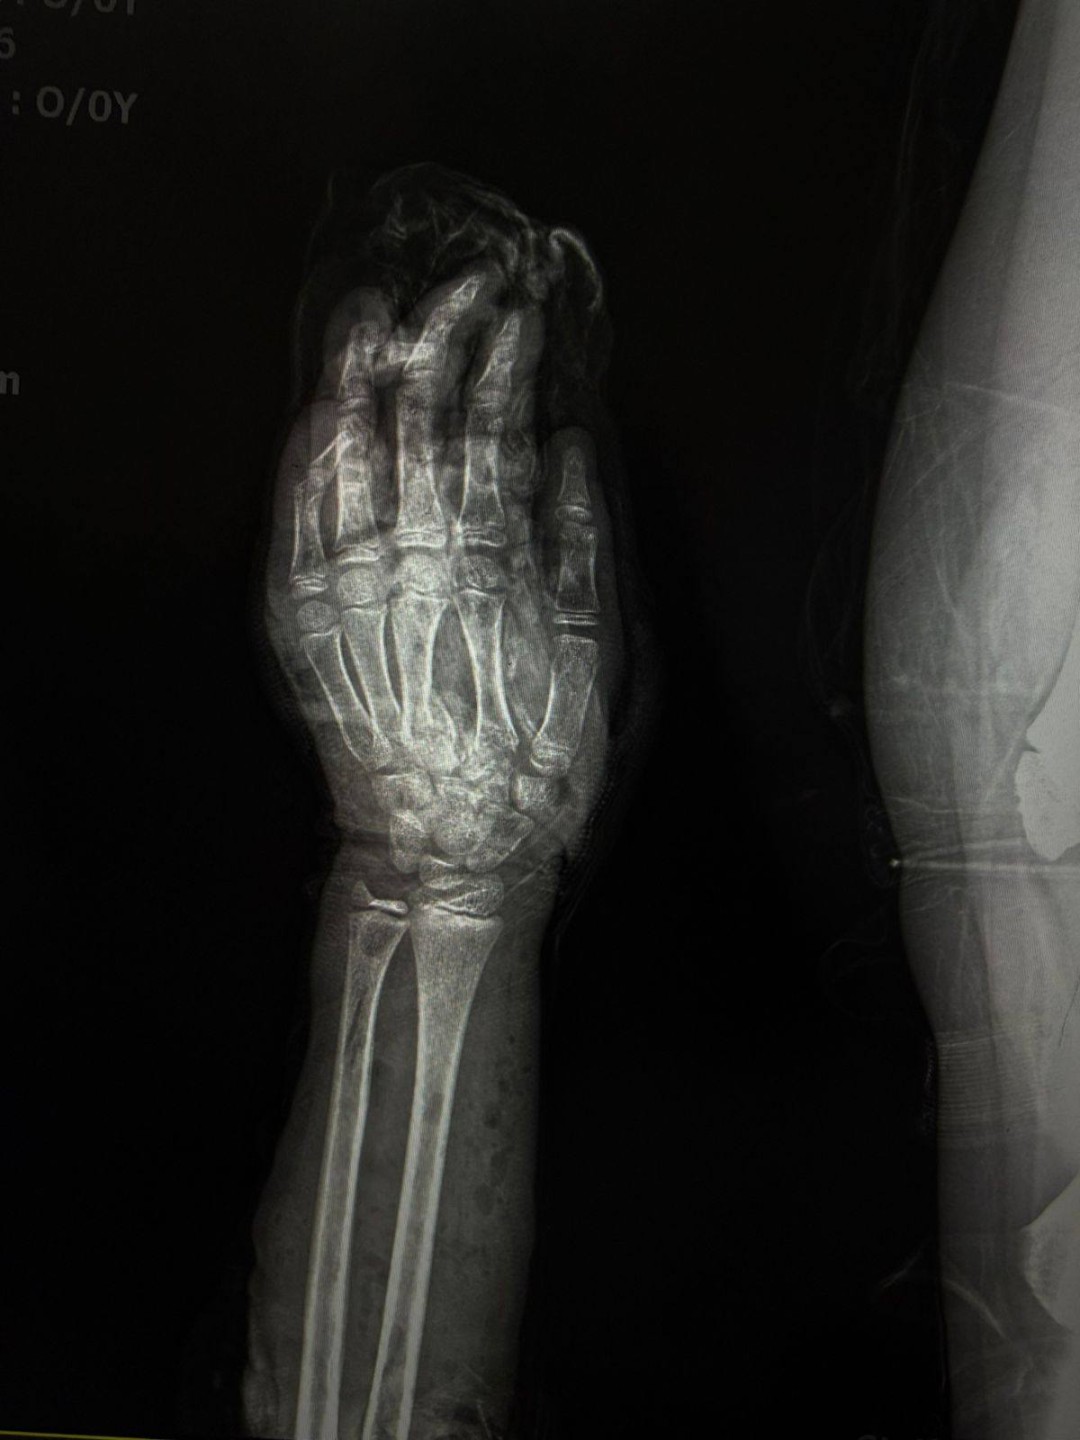

نجح فريق طبي متخصص بمستشفى الطوارئ الجديد بجامعة سوهاج، في إنقاذ ذراع طفل يبلغ من العمر 12 عامًا، عقب تعرضه لإصابة شديدة نتيجة حادث طاحونة قمح، أسفر عن تهتك كامل بأنسجة الذراع، وكسور متعددة بالأصابع، إلى جانب إصابة الأوتار والأعصاب.

وأشار الدكتور أحمد كمال، المدير التنفيذي للمستشفيات الجامعية ، إلى أن فريق وحدة جراحات اليد الميكروسكوبية قام بتثبيت الكسور الدقيقة بالأصابع، وتوصيل الأوتار والأعصاب المصابة، مع استكشاف الأوعية الدموية والتأكد من سلامتها، فيما تولى فريق جراحة التجميل إجراء رقعة جلدية لتعويض الجزء المتهتك المفقود من الذراع.